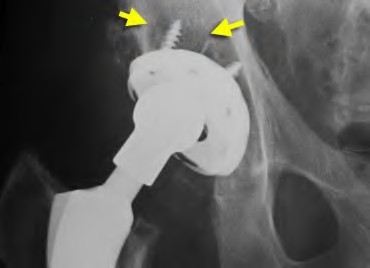

A 75-year-old man underwent total hip arthroplasty 10 years ago. He now reports mild groin pain which has been increasing lately. What is the most likely explanation for the finding in Figure A indicated with the arrows?

Osteolysis of the pelvis is a common complication associated with total hip arthroplasty. Osteolysis affects sockets with and without cement, and has been attributed to the biologic reaction to wear debris. With well-fixed cementless sockets, an expansile pattern of osteolysis is usually seen.

The radiographic appearance has a radiolucent area that starts at the implant-bone interface and expands into the cancellous bone away from the implant.

This pattern of osteolysis can be explained with the concept of effective joint space. This concept states that joint fluid and wear particles will flow according to pressure gradients and follow the path of least resistance.

The Level 5 review article by Chiang discusses osteolysis in further depth.